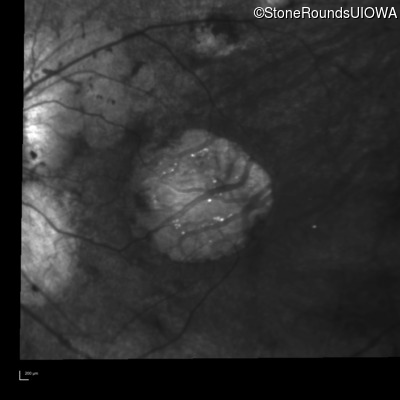

Infrared Fundus Photograph - Right - 20/125

Exemplar

Infrared Fundus Photograph - Left - 20/100 -1